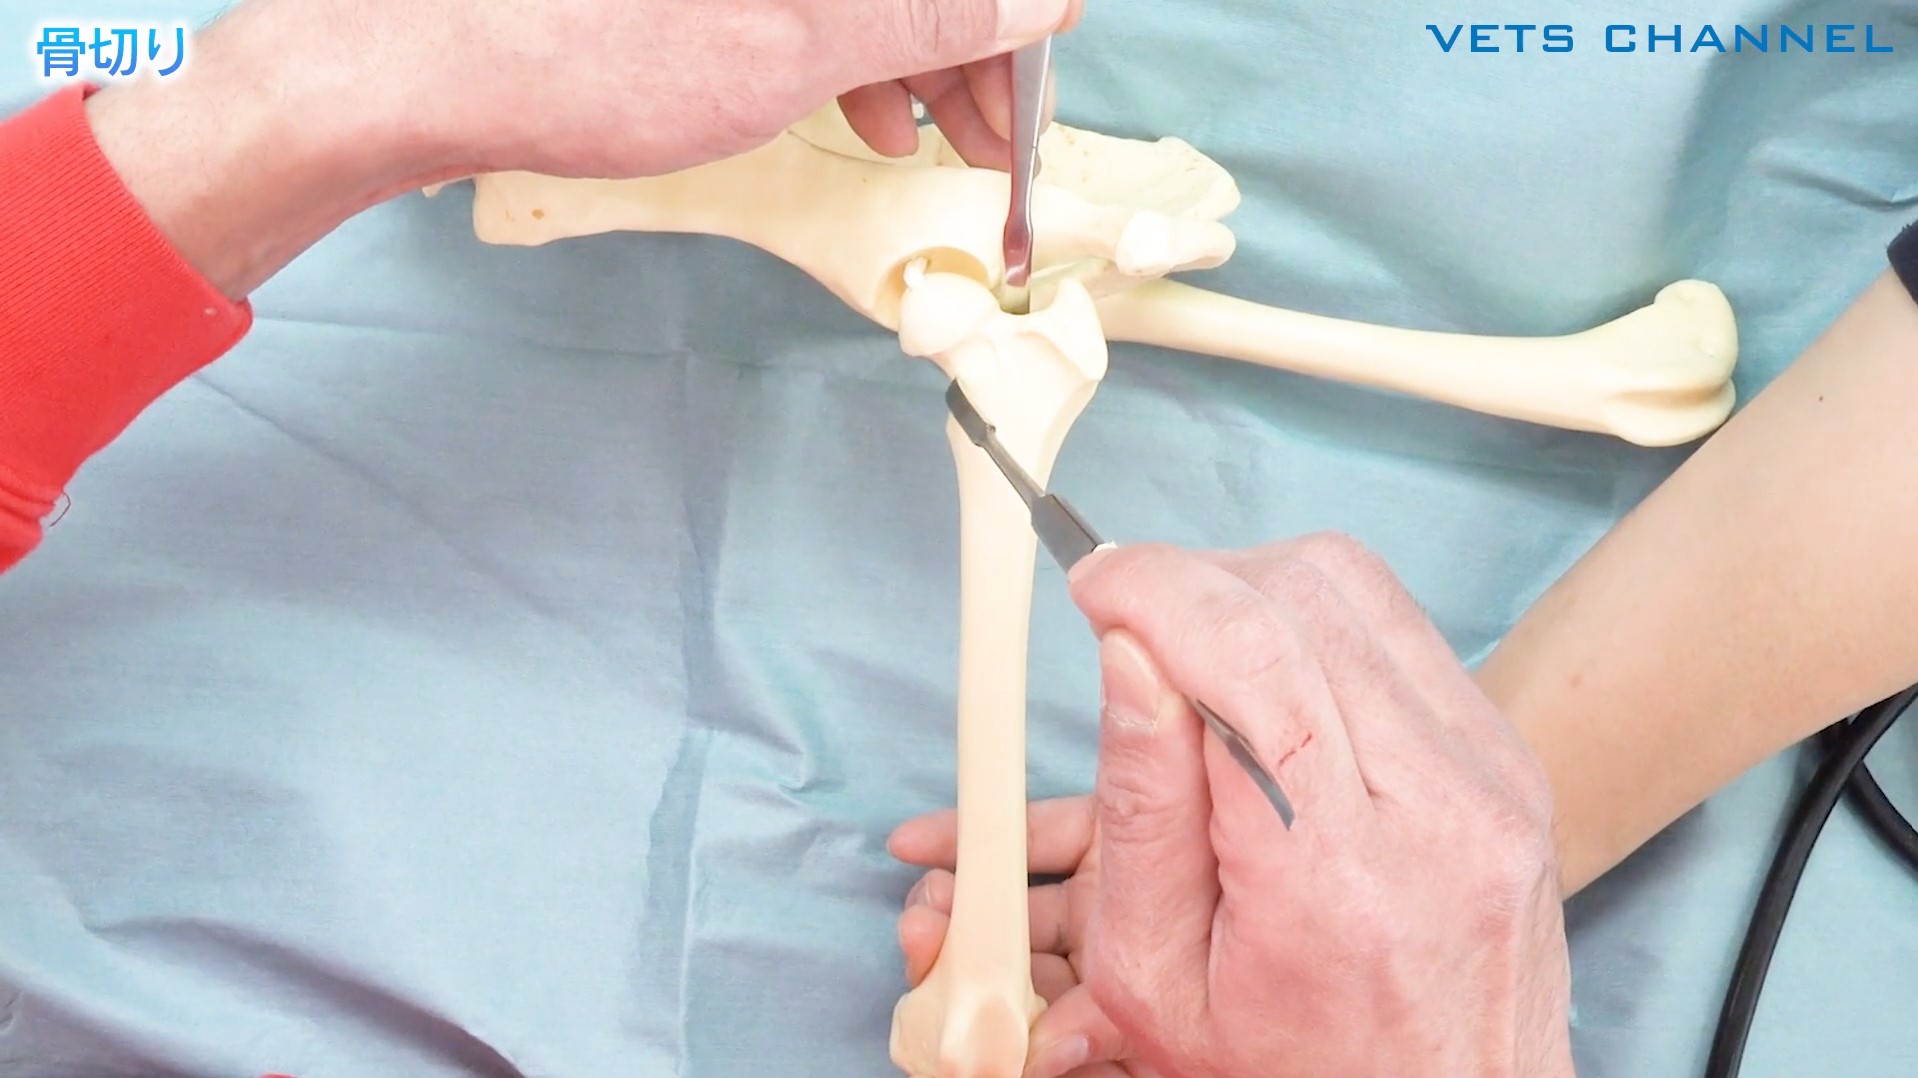

#小技「大腿骨頭切除術」から「骨頸部を取り残さない小技」

- テクニック

- 整形外科

- 犬

川合 智行先生(横浜山手犬猫医療センター)

14分

2024/11/15